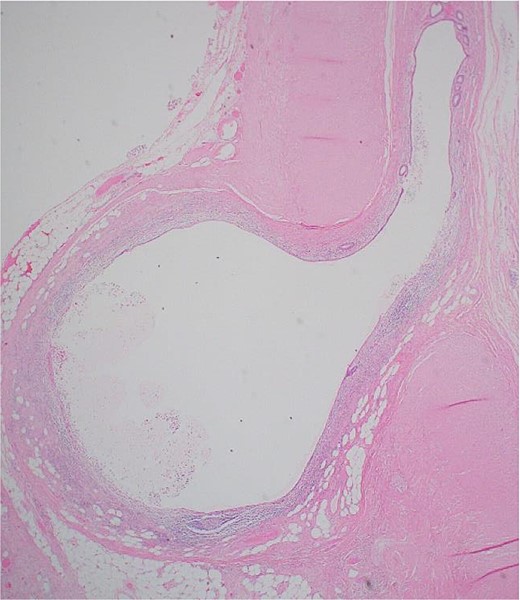

An image showing a whole-slide longitudinal section of the distal appendix demonstrating multiple outpouchings of mucosa through weak points of the muscular wall.

Postoperatively, the patient had an uneventful recovery and was discharged the next day with simple analgesia. Histopathology revealed an 8 × 1.2 cm appendix with a 3.5 × 2.5 cm distal bulge, filled with pus and multiple diverticula. Examination showed acquired appendicular diverticulosis with mucosal and submucosal outpouchings through the muscularis propria. The mucosa and diverticula were infiltrated by neutrophils extending to the submucosa and muscular wall, with inflammation reaching the mesenteric fibroadipose tissue. Reparative changes included edema, macrophages, and fibroblastic proliferation. The final diagnosis was appendicular diverticulosis complicated by acute appendicitis with an organizing abscess (Figs 6 and 7).